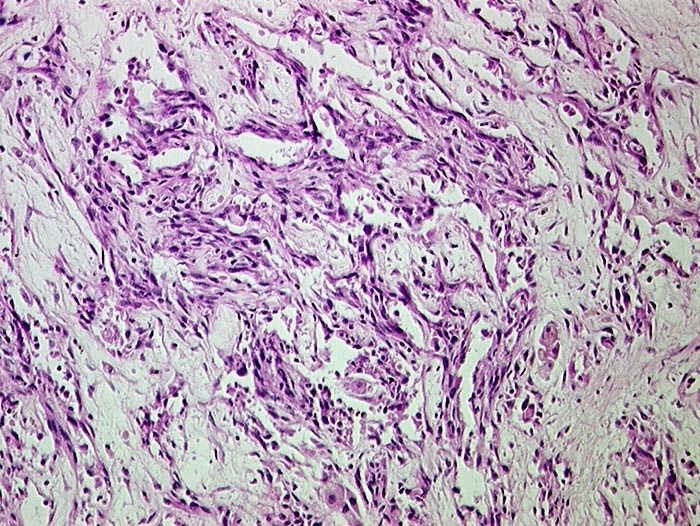

AP/ Angiosarkom der Leber

Angiosarkom der Leber

Pathologischer Befund